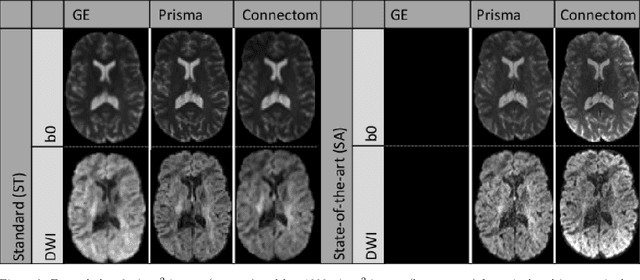

Abstract:Diffusion magnetic resonance imaging is a noninvasive imaging technique which can indirectly infer the microstructure of tissues and provide metrics which are subject to normal variability across subjects. Potentially abnormal values or features may yield essential information to support analysis of controls and patients cohorts, but subtle confounds affecting diffusion MRI, such as those due to difference in scanning protocols or hardware, can lead to systematic errors which could be mistaken for purely biologically driven variations amongst subjects. In this work, we propose a new harmonization algorithm based on adaptive dictionary learning to mitigate the unwanted variability caused by different scanner hardware while preserving the natural biological variability present in the data. Overcomplete dictionaries, which are learned automatically from the data and do not require paired samples, are then used to reconstruct the data from a different scanner, removing variability present in the source scanner in the process. We use the publicly available database from an international challenge to evaluate the method, which was acquired on three different scanners and with two different protocols, and propose a new mapping towards a scanner-agnostic space. Results show that the effect size of the four studied diffusion metrics is preserved while removing variability attributable to the scanner. Experiments with alterations using a free water compartment, which is not simulated in the training data, shows that the effect size induced by the alterations is also preserved after harmonization. The algorithm is freely available and could help multicenter studies in pooling their data, while removing scanner specific confounds, and increase statistical power in the process.